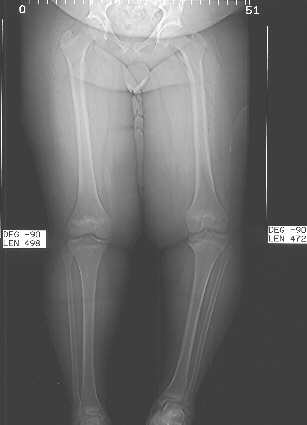

Islands

of densely packed hypertrophied cartilage cells, not in the usual

columnar organization is the typical histology.

Although

not an inherited problem often family members also have adolescent

tibia vara.